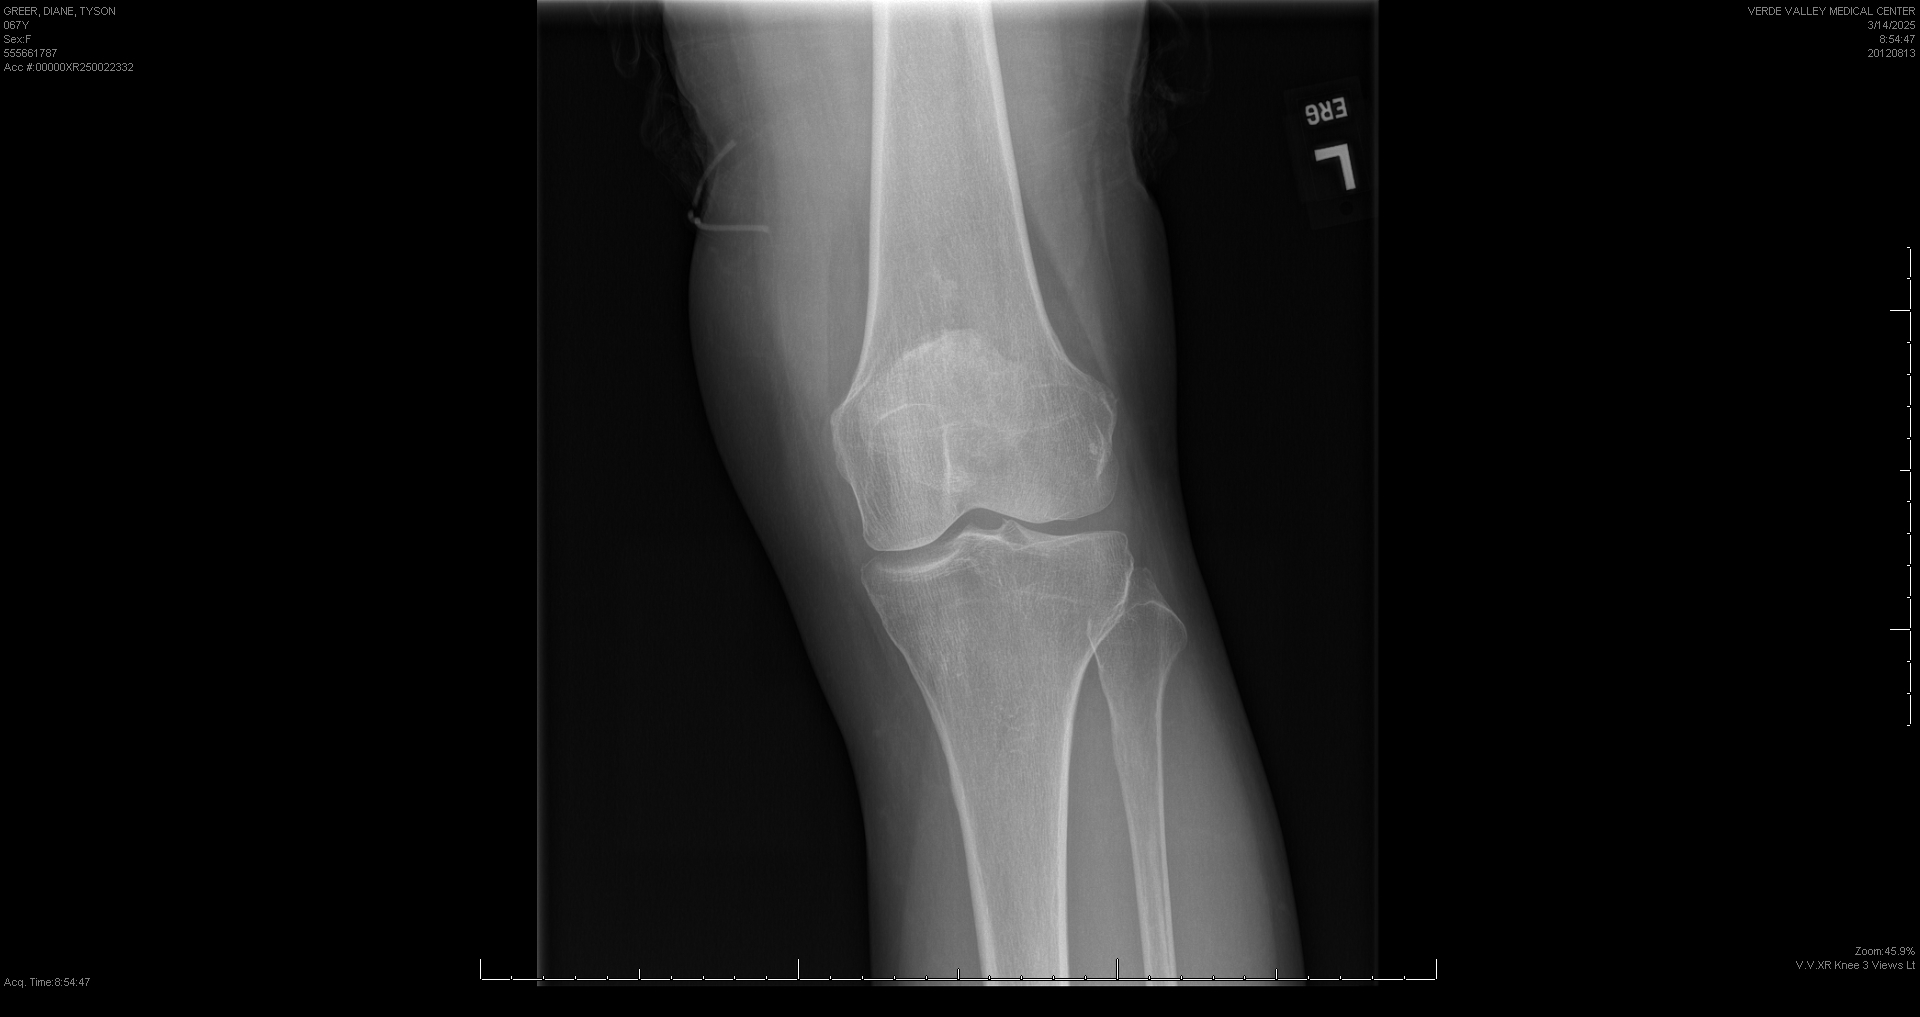

March 14, 2025

Front View

Result type: XR Knee 3 Views Lt Result date: Mar 14, 2025, 09:08 a.m. Result status: authenticated Performed by: ERIN GAFF Verified by: TERRENCE CAVANAUGH Modified by: TERRENCE CAVANAUGH Accession number: OOOOOXR20250022332

FINAL REPORT

X-RAY OF KNEE (LEFT), 3 VIEW(S): 3/14/2025 8:47 AM ORDERING PROVIDER: Physicians Flagstaff INDICATION: Injury, knee , Admit Reason: L KNEE PAIN. COMPARISON: None FINDINGS XR Knee 3 Views Lt Patient: Diane Greer DOB: May 07, 1957 SOFT TISSUES: Multiple calcific densities seen superior to the patella, probable quadriceps tendinitis. No joint effusion. BONES: No acute fracture. Normal mineralization. JOINTS: No dislocation. No significant arthritis. OTHER FINDINGS: None. IMPRESSION: Normal.